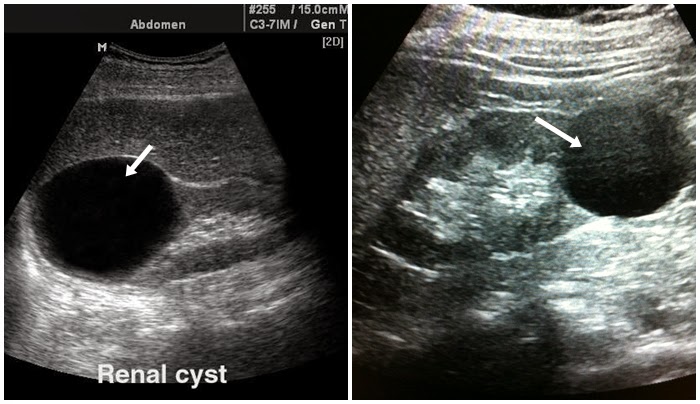

Usg ginjal dilakukan menjadi tes inspeksi buat mendeteksi kista. Dari mencocokkan keluhan, pemeriksaan fisik dan gambaran usg dokter anda akan bisa memperkirakan apakah kista ini membutuhkan operasi atau tidak. Dan ini lah salah satu gambaran kista.

Dengan usg, dokter dapat melihat bentuk, ukuran, letak, dan meninjau apakah kista berisi jaringan padat atau cair. Karena tidak sering timbul gejala penyakit kista, kista umumnya baru diketahui saat pasien menjalani pemeriksaan ultrasonografi (usg), atau pemeriksaan di daerah perut bagian bawah. Bila pada pemeriksaan pertama ditemui kista yang tak terlalu besar, dengan batasan 5 sentimeter.